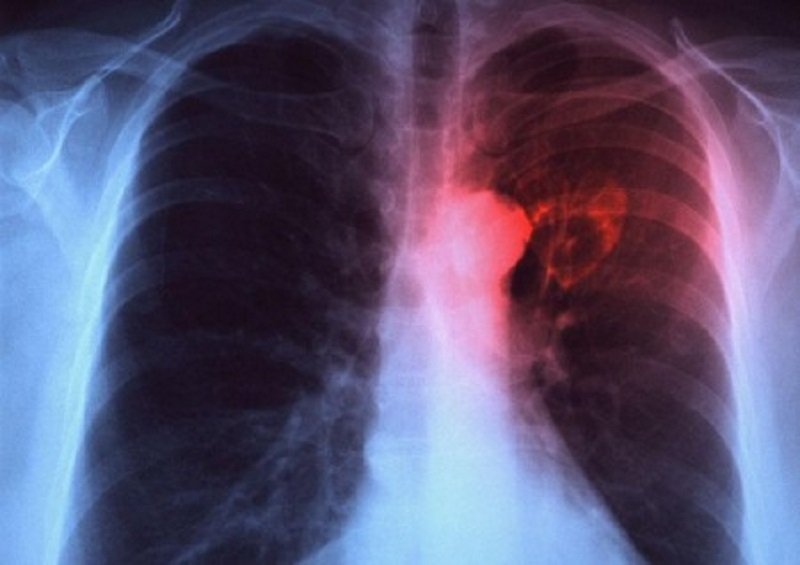

Uno dei mali che più affligge la nostra società di questi tempi è sicuramente il cancro. In particolare, quello ai polmoni è considerato il “big killer” per l’alto numero di vittime che miete ogni anno in tutto il mondo. Identificarlo non è solo difficoltoso, ma anche dispendioso.

Ogni anno in Italia sono 38.000 le persone a cui viene diagnosticato un cancro ai polmoni e di queste, 34.000 ne muoiono. Ma la percentuale si potrebbe drasticamente abbassare se solo ci fossero programmi di screening ad hoc per individuare il male già ai primi stadi.